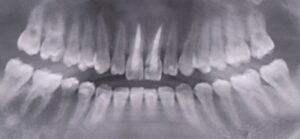

初診時に前歯が噛んでいない

インビザラインで失敗した23歳女性

初診時に奥歯が噛んでいない

ワイヤー矯正で全体の歯が噛んでいる